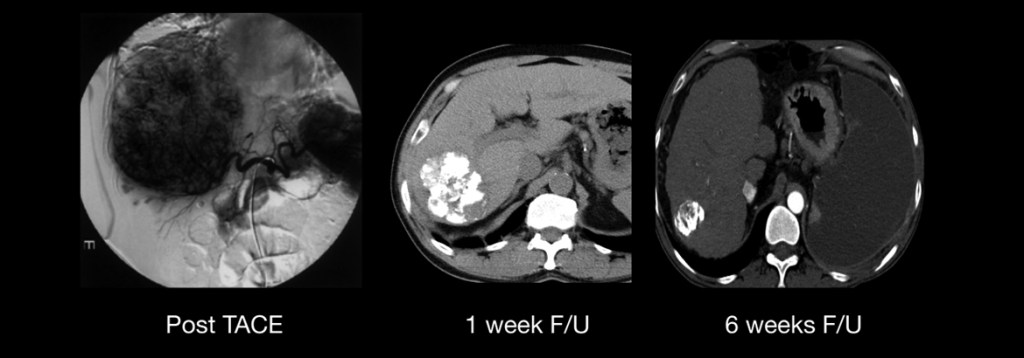

Fico feliz em dizer que, ao longo de duas décadas de atualizações no texto, tivemos um avanço realmente notável nos últimos anos. Surgiram novas modalidades de tratamento, que deixaram de ser apenas paliativos para muitas vezes ser curativos. Nos casos avançados, onde não havia praticamente nenhuma opção realmente eficaz, hoje temos imunobiológicos que podem conter o crescimento do tumor por anos. Felizmente, todas essas modalidades estão disponíveis aqui e o paciente brasileiro tem acesso ao que existe de mais moderno e eficaz recomendado por consensos científicos.